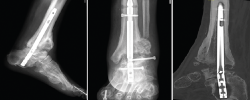

Figura 1. Imágenes radiográficas donde se observa rotura del clavo y extrusión del tornillo del astrágalo con ausencia de fusión. En la tercera imagen, proyección sagital de tomografía computarizada.

Se le realizó una ATTC mediante abordaje lateral transperoneal para el legrado de las articulaciones tibiotalar y subtalar, y fijación con un clavo tibiotalocalcáneo (TTC) retrógrado modelo Phoenix® (Zimmer Biomet) de 180 mm de longitud y diámetro de 11 mm. Ante el retraso de la consolidación, el clavo se dinamizó a los 6 meses de la implantación retirando el tornillo de bloqueo proximal. A los 15 meses se observó falta de fusión tanto de la articulación tibiotalar como subtalar y rotura del clavo con extrusión del tornillo de bloqueo del astrágalo (Figura 1).